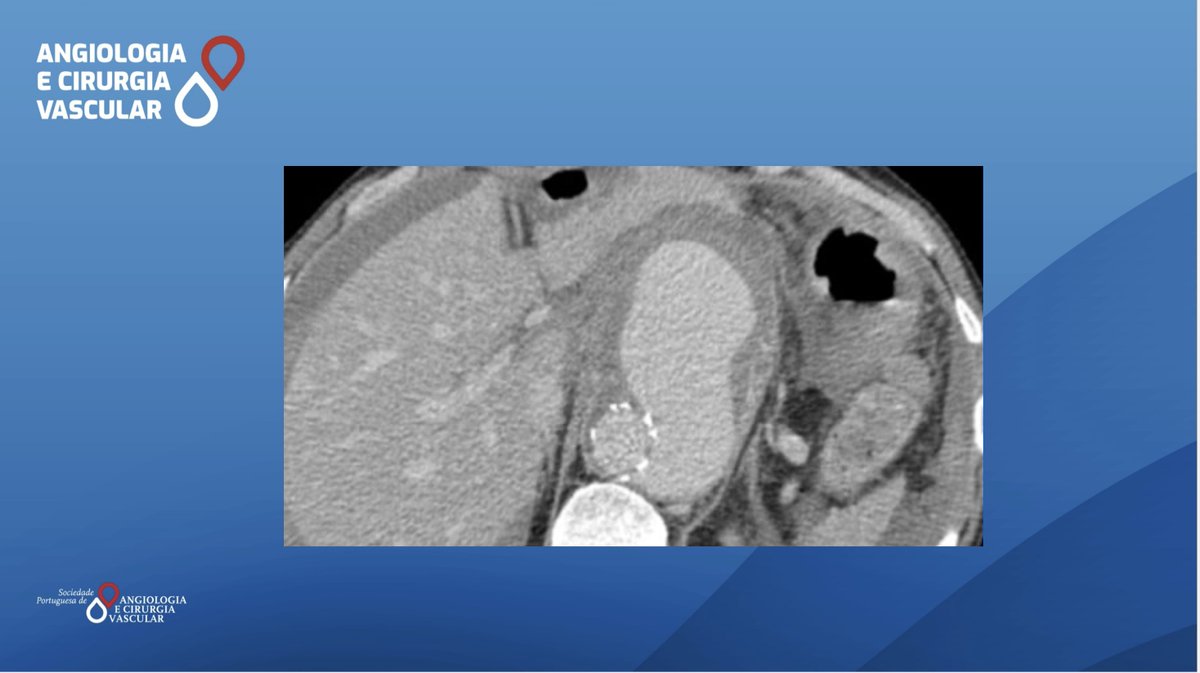

Open surgery and an aorto- aortic interposition with bovine pericardium patch was the treatment choice of Bento R. et al. Read more here: acvjournal.com/index.php/acv/… #spacv #vascularsurgery #mycoticaorticaneurysms #vascularinfections ESVS Society for Vascular Surgery Vascular News